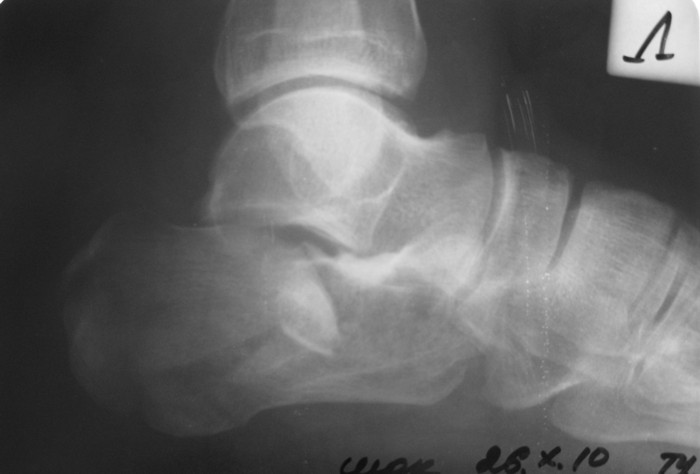

Уважаемые коллеги!Мужчина, 47 лет. Диагноз: Кататравма (26.10.10г. падение с высоты 2го этажа). Открытый оскольчатый внутрисуставной перелом дистального метаэпифиза лучевой кости, перелом шиловидного отростка локтевой кости левого предплечья со смещением отломков, закрытый оскольчатый внутрисуставной перелом дистального метаэпифиза лучевой кости, перелом шиловидного отростка локтевой кости правого предплечья со смещением отломков. Закрытый оскольчатый внутрисуставной перелом левой пяточной кости, закрытый оскольчатый внутрисуставной перелом дистального метаэпифиза обеих костей правой голени со смещением отломков, закрытый компрессионно-оскольчатый перелом тела L2 позвонка с болевым вертеброгенным синдромом. 						Голень и предплечья синтезированы АВФ в ургентном порядке. В настоящее время состояние пациента стабильное, к оперативному лечению соматически готов.		Во время клинического разбора мнения разделились: 1) открытая репозиция, МОС пяточной пластиной 2) гипсовая иммобилизация 3) ЧКО аппаратом внешней фиксации как репозиционный и окончательный вариант остеосинтеза. 4) необходимость СКТ? 	Коллеги, пожалуйста, интересует ваше мнение относительно тактики лечения,  необходимого перечня рентгенологического обследования оскольчатого внутрисуставного перелома пяточной кости и сроков выполнения предполагаемой операции. Просим высказаться относительно необходимости выполнения СКТ как важного этапа диагностики. Пациент будет повторно представлен на ближайшем клиническом разборе  (приветствуются примеры аналогичных клинических случаев, ссылки на современную литературу и диссертационные работы).Заранее благодарим!С уважением,А.В.ВладзимирскийДНИИТО